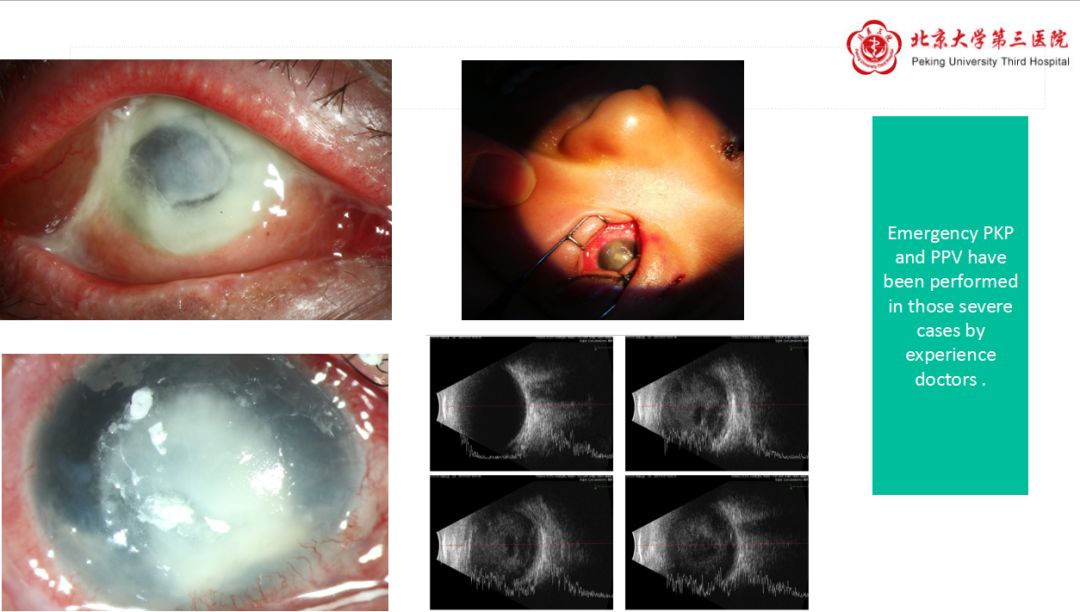

现阶段临床经验丰富的医生对于重症眼内炎病例均采取急症PKP和PPV治疗。毫无疑问,严重的角膜炎导致的严重的眼内炎患者,尤其是在创伤后迅速发展为进行性眼内炎的患者最常见的后果是视力预后差、低眼压、眼球萎缩,有些甚至需要眼球摘除。因此,此类患者需要立即进行PPV或者PKP治疗。

冯云教授分享了多个临床案例,阐述了重度眼内炎治疗中进行急诊PKP和PPV的重要意义。目前临床中常见病因包括组织污染、外伤性感染和内源性感染。有角膜感染病灶的眼内炎立即进行角膜移植是去除病变的关键。玻璃体腔内行PPV是清除脓肿的一项必要手段,但在脓肿遍布视网膜表面的严重病例中,不必过于纠结于将表面的脓菌切除干净,在感染的视网膜受累状态组织糟脆,容易造成医源孔,注射抗生素对控制感染的效果要比把脓肿全部切除干净更有效。仔细的PPV治疗避免孔源性视网膜脱离(RRD)从而避免硅油填充,因为一旦硅油填充,眼内循环较差,俯卧位睫状体附近毒素更为集中,因此这也是改善预后的关键所在。